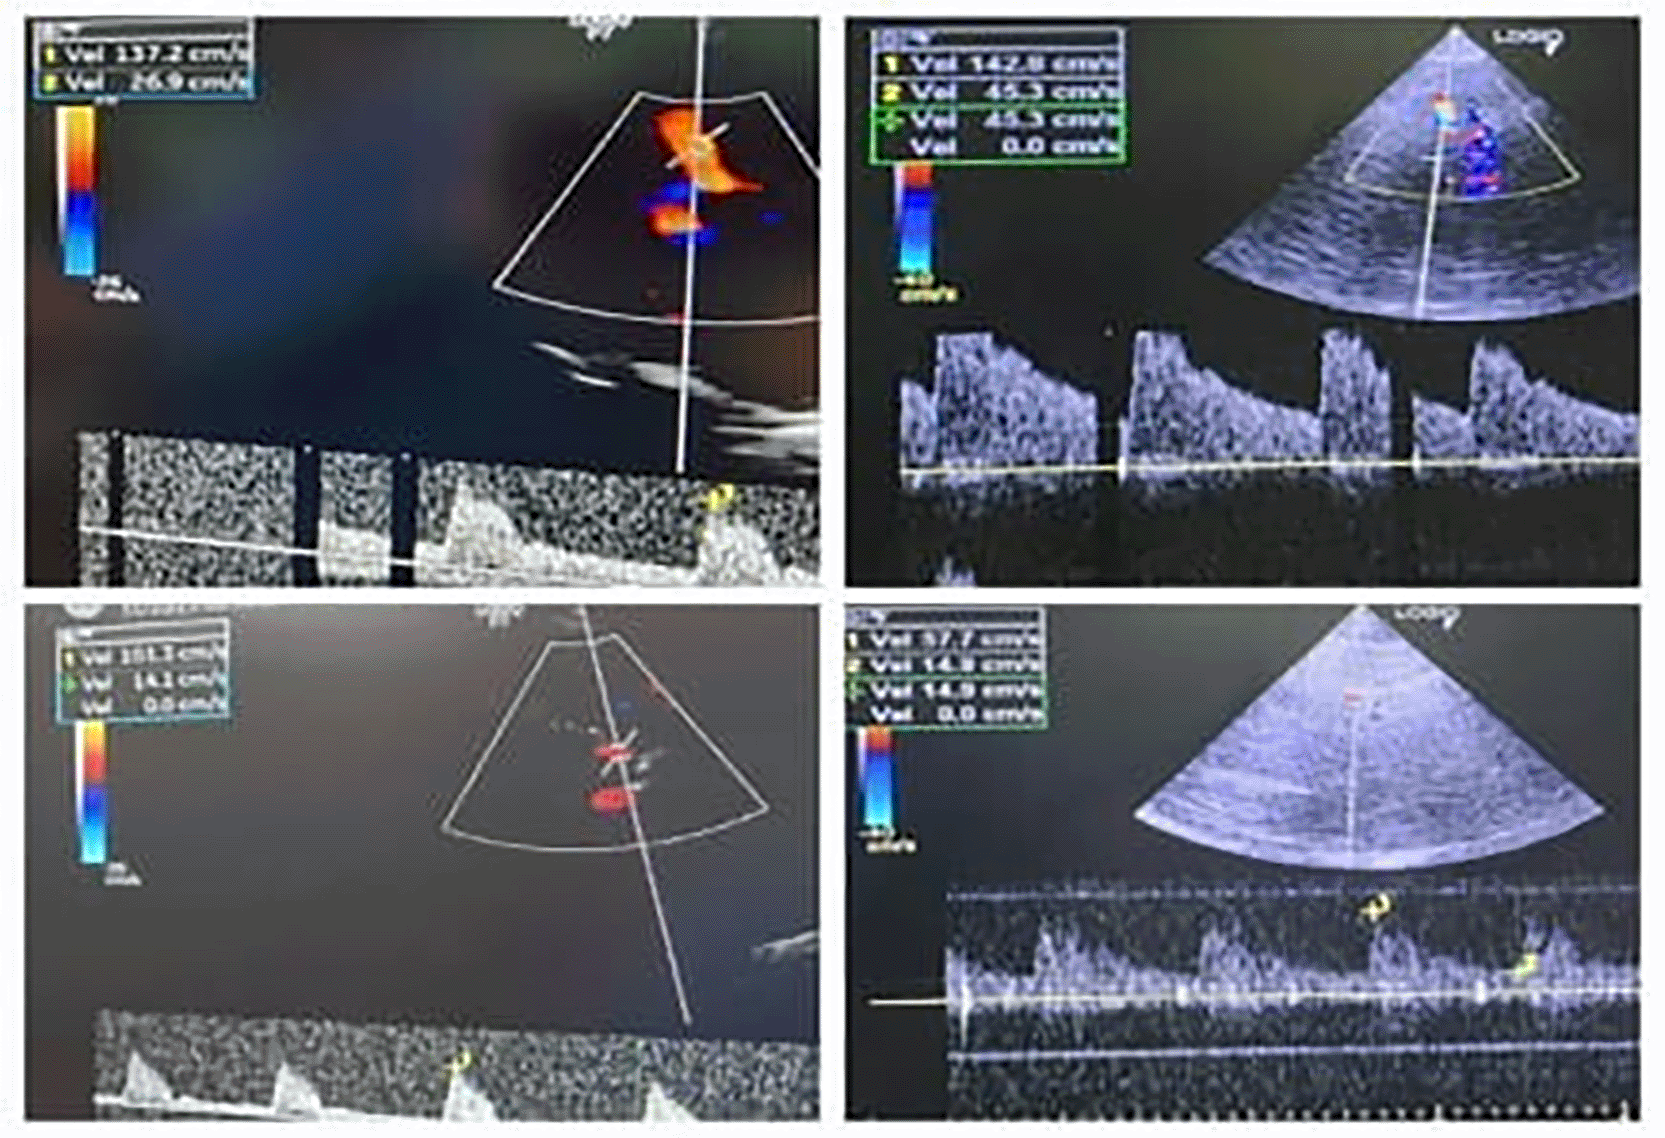

Perioperative ICP was monitored via bedside ultrasound using optic nerve sheath diameter (ONSD) and transcranial Doppler (TCD). Baseline ONSD values were elevated (OD: 0.62 mm, OS: 0.55 mm), and TCD showed high pulsatility index (PI of MCA) values 1.73 on the right (~ ICP 17.63) and 2.02 on the left (~ ICP 20.79). After induction and magnesium infusion, ONSD decreased (OD: 0.42 mm, OS: 0.46 mm), and PI improved (right: 1.2; left: 1.4), reflecting reduced ICP and improved cerebral compliance ( Table 2).

Real-time ultrasound monitoring of ICP was performed using optic nerve sheath diameter (ONSD) and transcranial Doppler (TCD). Initial ONSD values were elevated (OD 0.62 mm; OS 0.55 mm), and pulsatility indices from the middle cerebral arteries indicated raised ICP (PI: right 1.73; left 2.02). Post-MgSO4 administration, ONSD decreased (OD 0.42 mm; OS 0.46 mm), and PI improved.

Bedside ultrasound monitoring of optic nerve sheath diameter trends has been validated as a reliable non-invasive surrogate for intracranial compliance in pediatric populations, particularly in neurosurgical and neurocritical care pathways. Representative pre- and post-induction optic nerve sheath diameter measurements illustrating directional change rather than absolute ICP quantification are shown in Figure 1. Directional reduction of pre-induction elevated ONSD values (from 0.62 mm right; 0.55 mm left to <0.5 mm range post-induction) adds physiologic coherence to suspected ICP improvement and supports individualized intraoperative titration logic, especially when interpreted as trend-based compliance directionality rather than absolute numeric diagnosis.16,17 Transcranial Doppler assessment of middle cerebral artery pulsatility indices is a validated method for reflecting changes in cerebral compliance and perfusion directionality in children, including in traumatic and neurocritical populations. Corresponding changes in middle cerebral artery flow dynamics assessed by transcranial Doppler are illustrated in Figure 2. The observed reduction from pre-induction elevated PI (2.02; 1.73) into improved ranges (1.2; 1.4) remains consistent with literature-mapped pediatric Doppler–compliance trending, reinforcing physiologic plausibility without making overstatements that transcend case-level inference.16,18,19